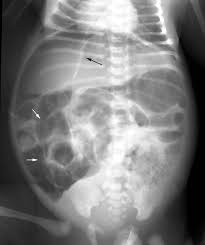

Rigler Sign

See the outline of the small and large bowel outlines - outlined by intraperitonial gas

Free air - Best seen in the right upper quadrant